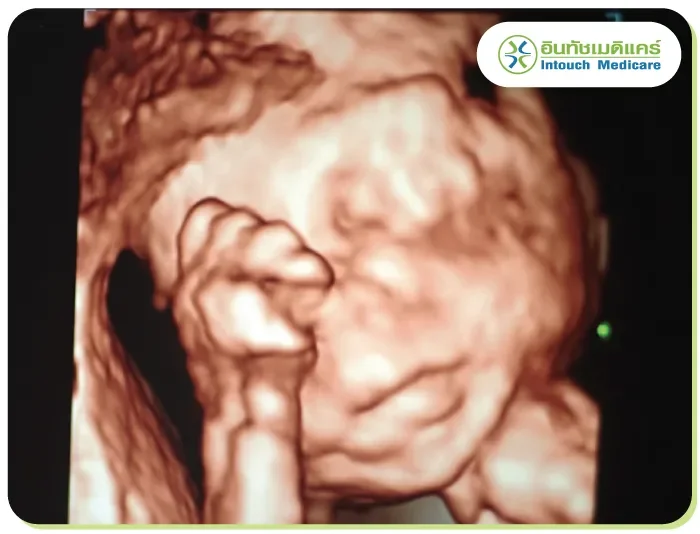

It is similar to 3D ultrasound, but with more advanced processing that creates real-time, moving images. It shows detailed, lifelike motion, making it increasingly popular for medical use, especially in observing the development of a fetus.

Obstetric ultrasound is used during pregnancy to calculate the due date, detect multiple pregnancies, diagnose ectopic pregnancies, and check fetal health. It also screens for congenital disabilities, checks amniotic fluid levels, and assesses the placenta's position.

It can determine the gestational age, recognize the fetus’s movement and heart rate. 4D examination will be more suitable. Private hospitals or clinics will have 4D services that are more affordable and meet a wider range of needs.